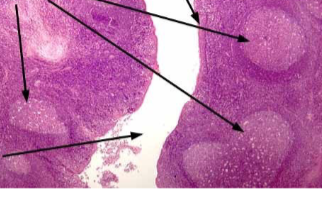

Peyer's patches

intestinal lymph node